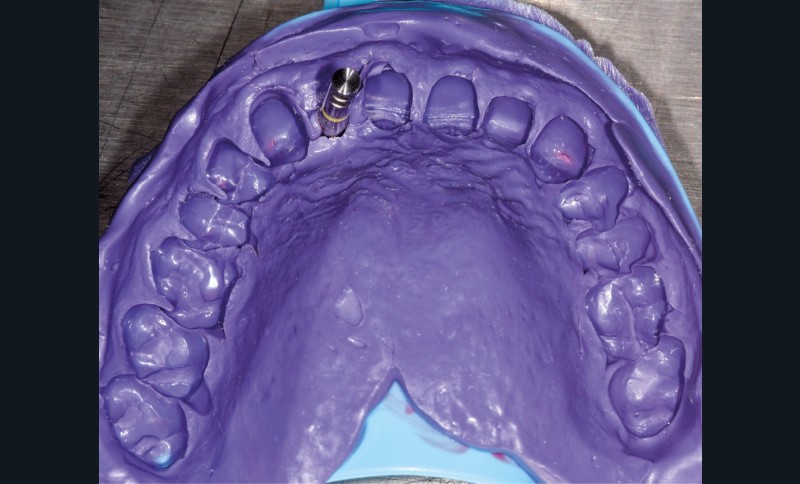

Un patient de 62 ans se présente en consultation afin de réaliser les coiffes prothétiques des dents 12 et 22. La 12 présente une restauration par prothèse transitoire non adaptée. Un implant au niveau de la 22 a été posé par un autre praticien selon une technique chirurgicale en deux temps. Le praticien a adressé le patient pour la réalisation prothétique. L’option de bridge collé cantilever mono ailette n’avait pas été retenue ou proposée selon une technique chirurgicale en deux temps. Le patient souhaite rétablir l’esthétique et la fonction de ces deux dents uniquement.

La proposition thérapeutique retenue par le patient est donc une réhabilitation par couronne céramique sur 12 (dento-portée) et 22 (implanto-portée). Ce choix thérapeutique impose de concevoir des dents qui s’intègrent au mieux dans l’harmonie du sourire, tout en étant conscient des limites d’un tel traitement.